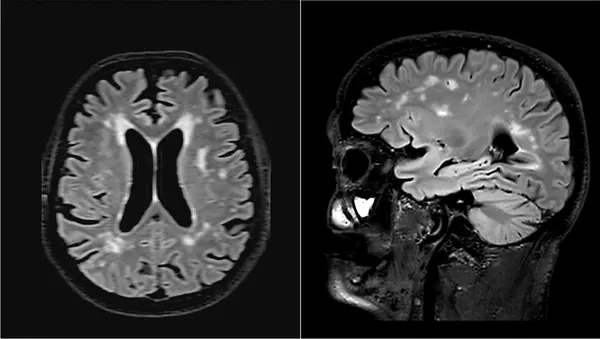

Сосудистые нарушения. Наиболее распространенная причина нарушения походки у пожилых людей. Исследования с использованием КТ и МРТ показали, что у людей с возрастными изменениями ходьбы обычно наблюдаются поражения белого вещества или лакунарные инфаркты.

Участники исследования согласились на ежегодные клинические оценки и посмертное донорство мозга. Вскрытие показало, что ухудшение ходьбы, которое предшествовало когнитивным нарушениям, было связано не с патологией болезни Альцгеймера, а с микроинфарктами. Это еще раз подтверждает связь между возрастными изменениями походки и сопутствующей цереброваскулярной патологией.